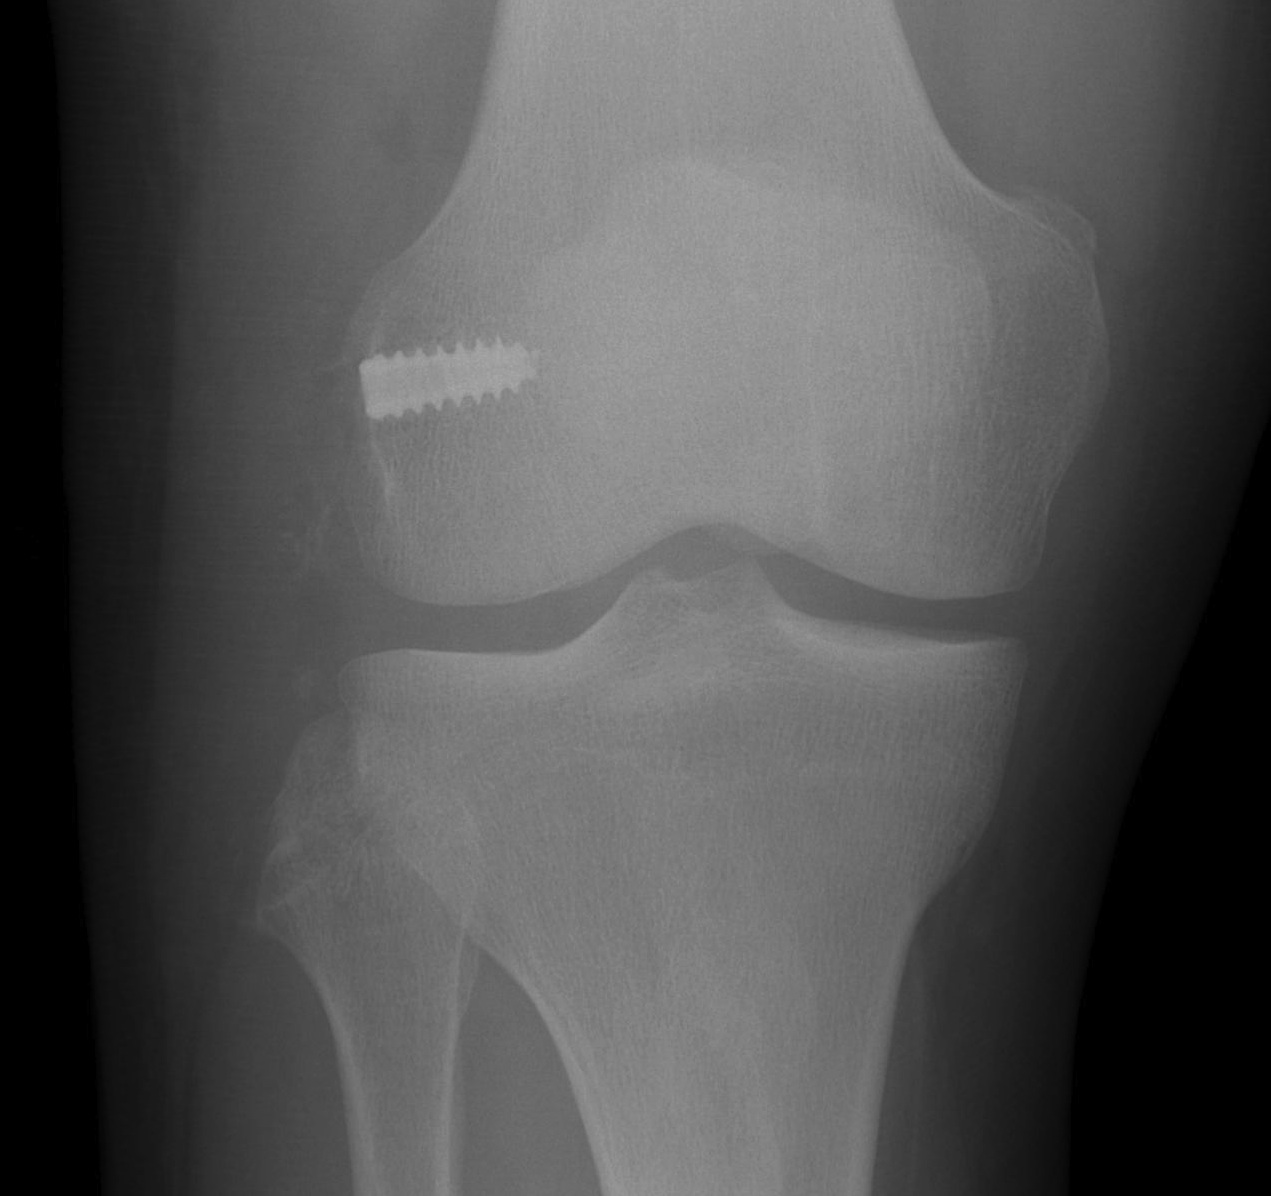

Left knee with LCL and popliteus tunnels and screw fixation of grafts